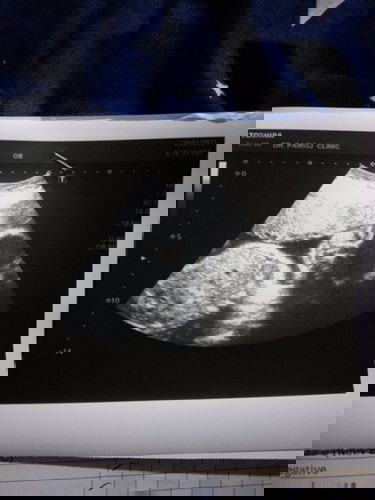

บ้านนี้ 27w4d น้ำหนักลูก1055กรัม บ้านอื่นน้ำหนักลูกได้เท่าไหร่กันค่ะ

หมอบอกน้ำหนักลูกน้อยไป

น้ำหนักเกินเกณฑ์เเล้วเอาที่ไหนมาน้อยอ่ะหมอ😅😅 ของเราตอน28wยังเเค่1010gเองค่ะ เเค่ตามเกณฑ์ไม่น้อยมากๆๆเลยหรือ????

ตอนนั้น27+2น้องหนัก1315 ตอนนี้28+6ยังไม่รุ้ค่ะต้องรอไปหาหมออีกทีค่ะ